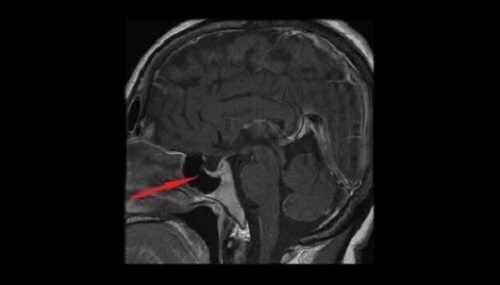

Vasopresina, cunoscută și sub denumirea de hormon antidiuretic sau ADH, este secretată de nucleele magnocelulare ale hipotalamusului. De acolo, aceasta trece în neurohipofiză și ajunge în sistemul circulator. Vasopresina ajută la reglarea cantității de lichide din organism prin controlul cantității de apă excretate de rinichi. În acest articol, vom analiza caracteristicile și efectele vasopresinei.

Nivelurile scăzute ale hormonului antidiuretic vor face ca rinichii să excrete excesul de apă. Volumul de urină va crește și va duce la deshidratare și la scăderea tensiunii arteriale. Așadar, nivelurile scăzute de hormon antidiuretic pot indica deteriorarea hipotalamusului sau a glandei hipofizare sau apariția polidipsiei primare.